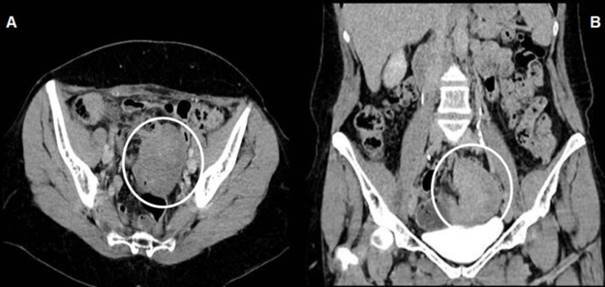

Como consecuencia de la duda sobre el origen de la tumoración, se solicitó tomografía de abdomeny pelvis con contraste intravenoso que muestra una masa sólida, redondeada, bien delimitada, de 75 x 55 mm, heterogénea, lateralizada a izquierda que capta medio de contraste, apoyada sobre la vejiga, comprimiendo y desplazando estructuras del tubo digestivo adyacentes (figura 1 a y b).

Figura 1: A) tomografía de pelvis, corte transversal: masa sólida, de 75 x 55 mm, heterogénea, que no capta el contaste, lateralizada a izquierda, comprime y desplaza las estructuras digestivas. B) corte frontal: tumoración sólida lateralizada a izquierda, apoyándose sobre la vejiga.